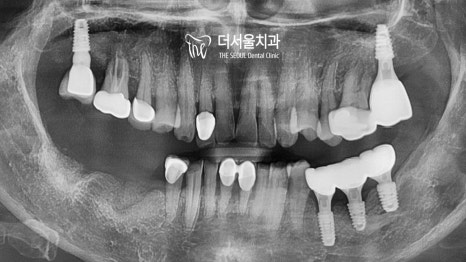

다행히 어려운 과정이었지만

별다른 문제 없이 마무리가 되었네요.

오른쪽을 진행하려는 그 찰나에 결국 빠져버렸습니다.

그래도 잘 버텨주어서 참 다행이네요.

이쪽도 별반 다르지 않았기에

똑같이 뼈이식 임플란트 로 개선을 도왔습니다.

최종 보철을 올려드린 모습을 보면

텅텅 비어있던 곳이 새하얗고 예쁜 크라운으로

오밀조밀 잘 채워져 있습니다^^